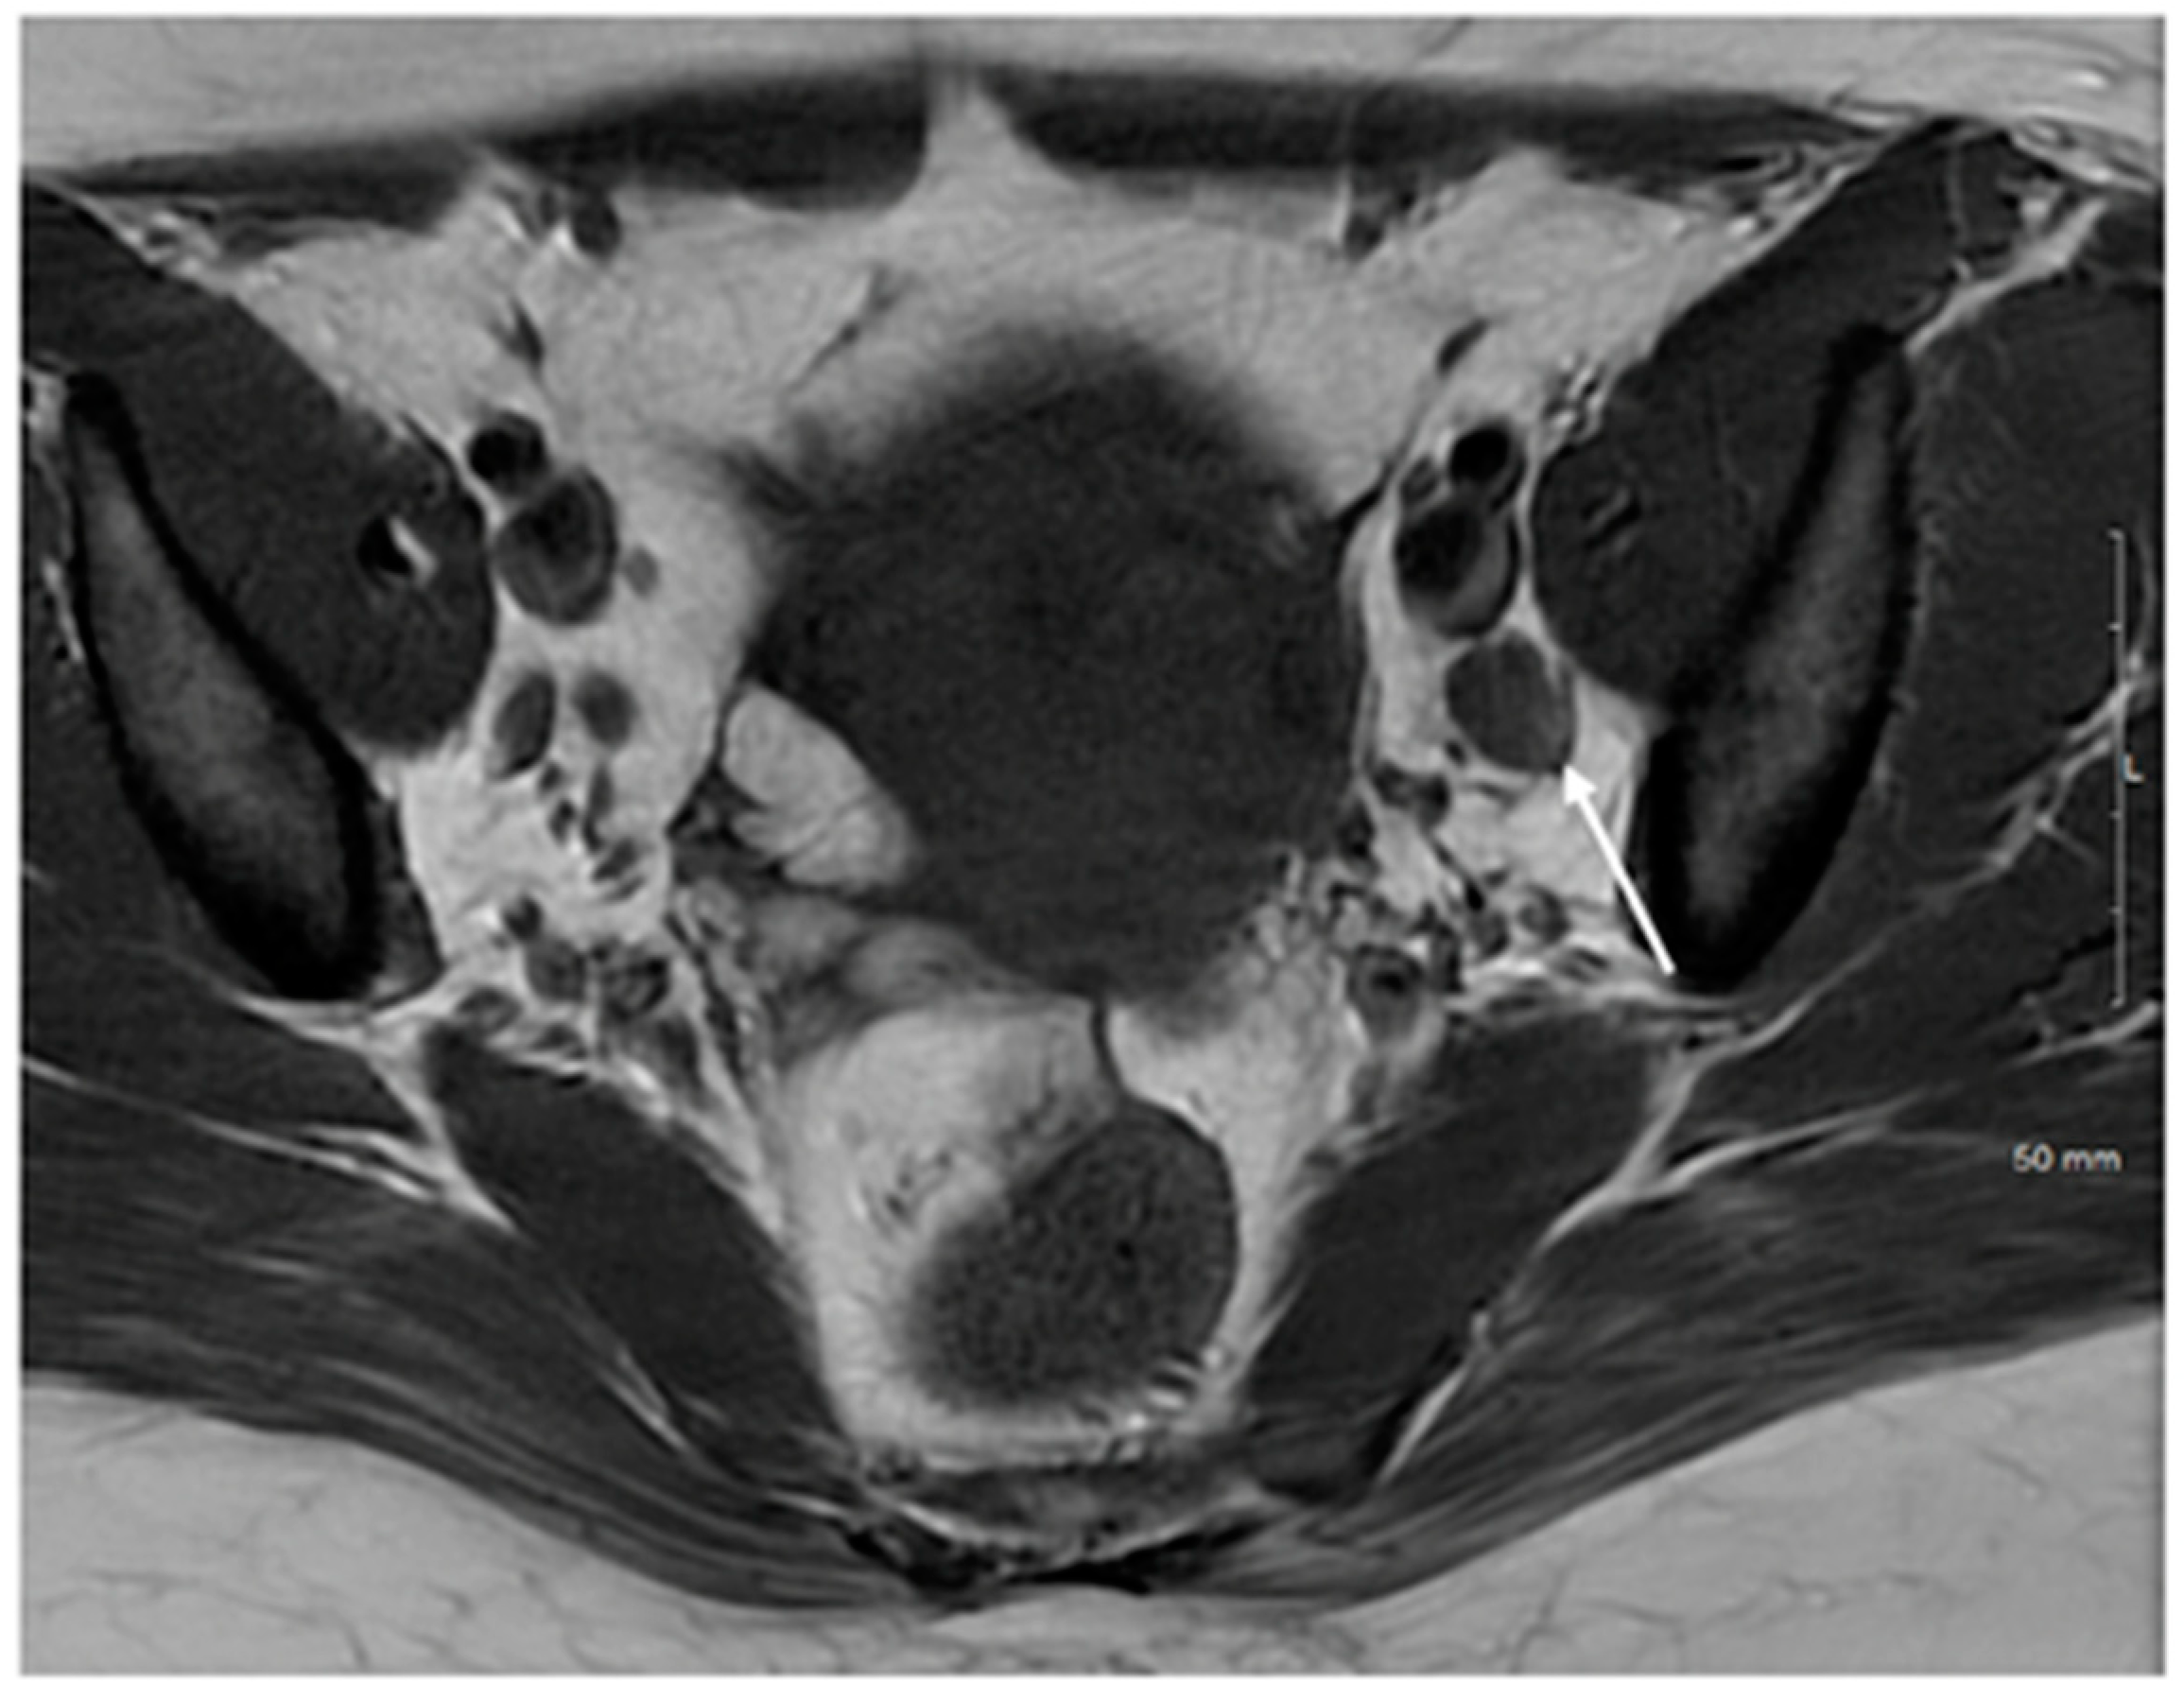

| Stage IV | Spread to adjacent and distant organs |

| IVA | Rectal or bladder involvement |

| IVB | Spread to distant organs outside the pelvis |